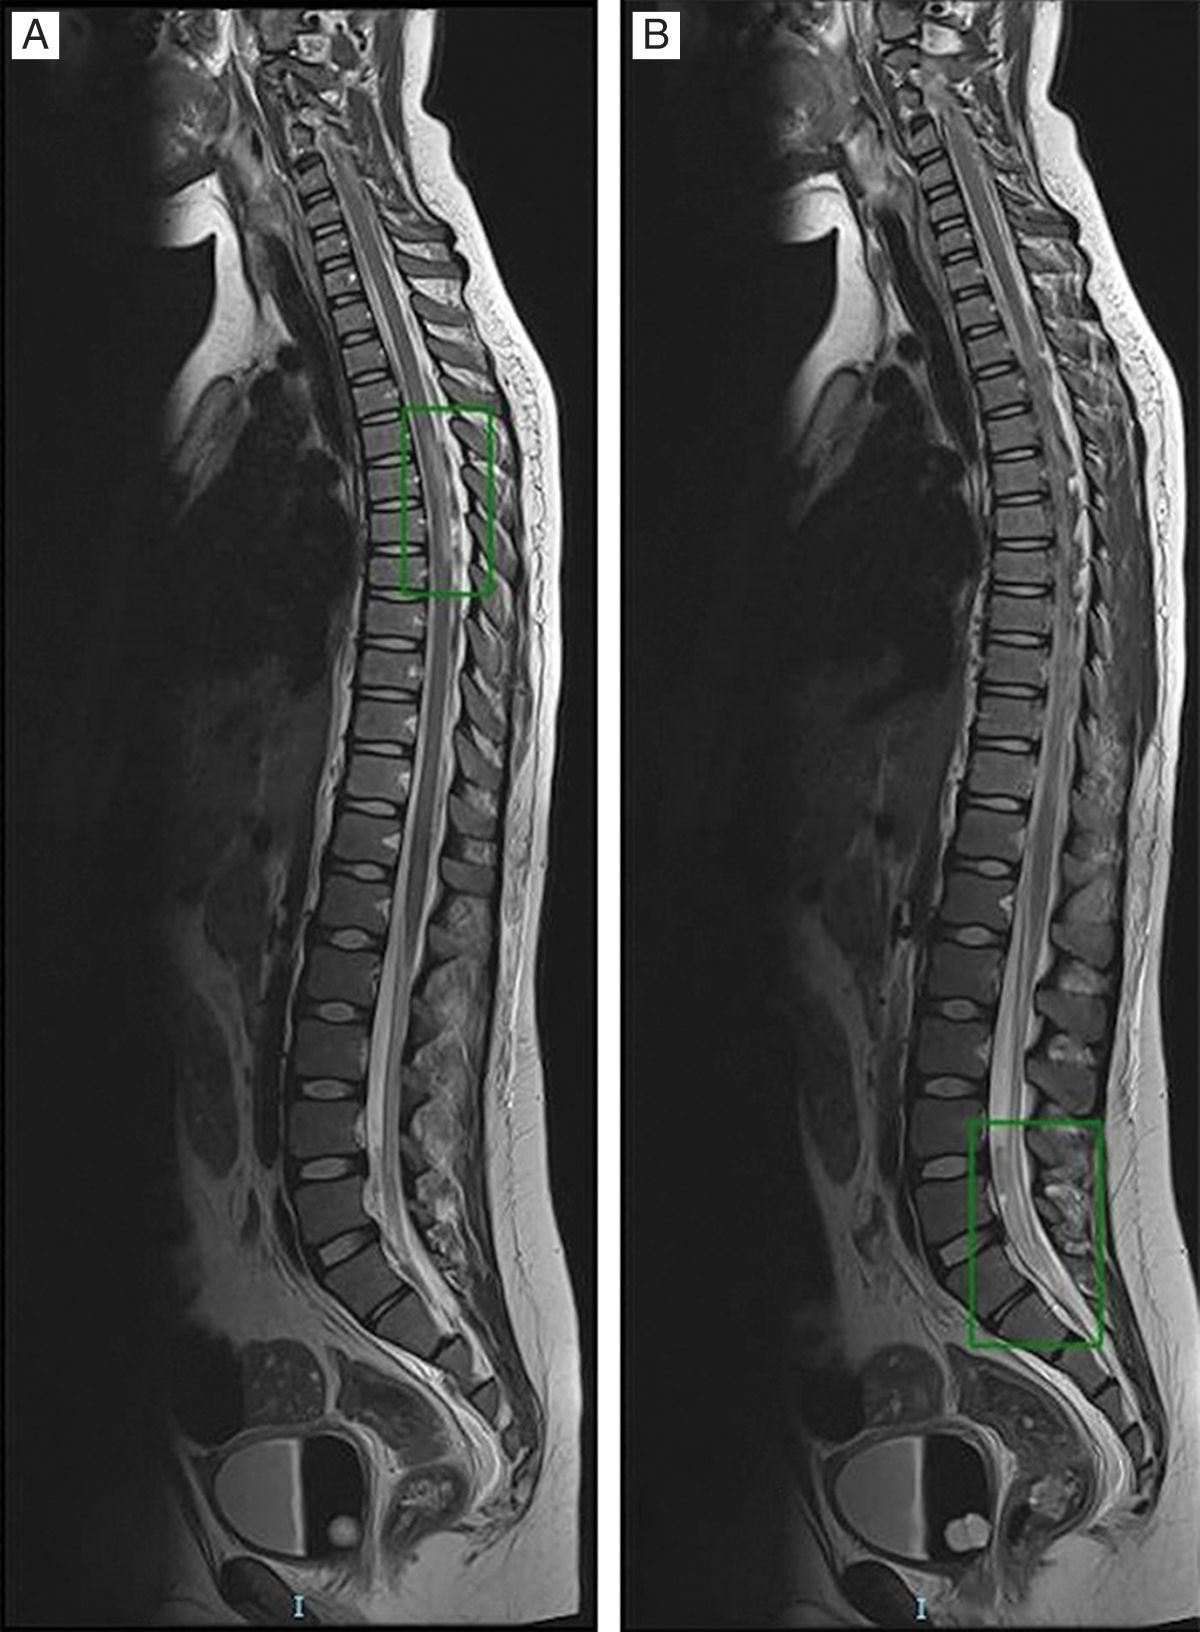

Given the poor response, a magnetic resonance (MR) scan was requested (Fig. 1A) that showed signs of infratentorial meningitis (Fig. 1B), generalised ventriculitis and supratentorial ischaemic encephalitis. At 5 days, once symptoms had improved, the patient was extubated and exhibited flaccid paraparesis with absent reflexes and numbness and cauda equina syndrome. The MRI of the scan was compatible with transverse myelitis1 (Fig. 2A) and evinced the presence of purulent material in the thecal sac with cauda equina radiculitis2 and arachnoiditis (Fig. 2B).

Spinal cord involvement suggested (A) acute transverse myelitis (longitudinal extensive involvement with T2 hyperintensity over more than 2/3 of the cord thickness), associated with (B) inflammatory-infectious radiculitis of the cauda equina and purulent material at the distal declive portion.